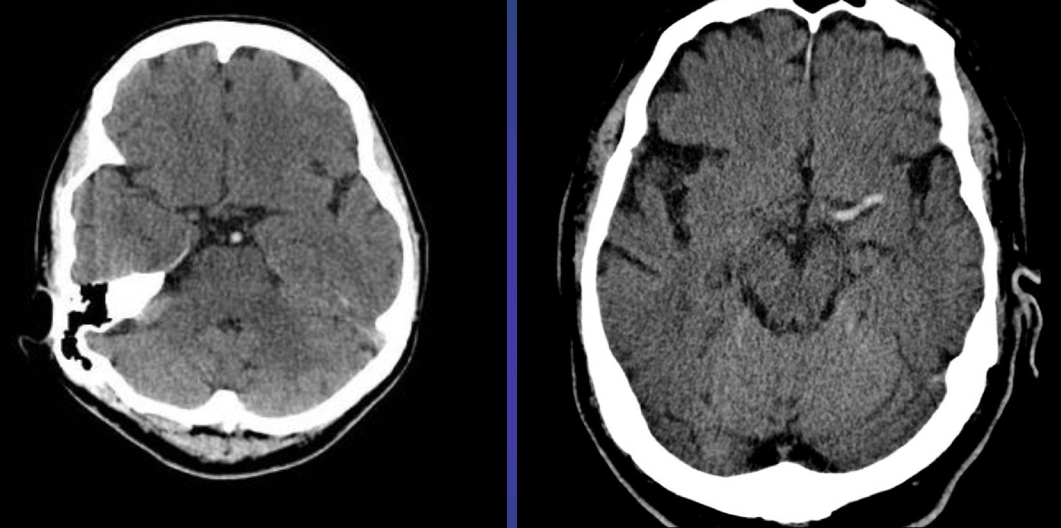

CT Brain IN EMERGENCY

Epidural hematoma

- Convex inner margin (lens-shaped)

- High density area

CT brain - Acute subdural hemorrhage

- crescent shape

CT brain - Chronic subdural hemorrhage

- Concave

CT brain - Acute on chronic subdural hematoma

- Inner margins are concave

Intracerebral hemorrhage

Infarction appear hypodense on CT without contrast

Sign? Hyperdense sign in stroke; LT Middle cerebral artery hyperintense

Y

Dense basilar artery and middle cerebral arteries on CT

Thrombus in vessel is hyperdense relative to flowing blood